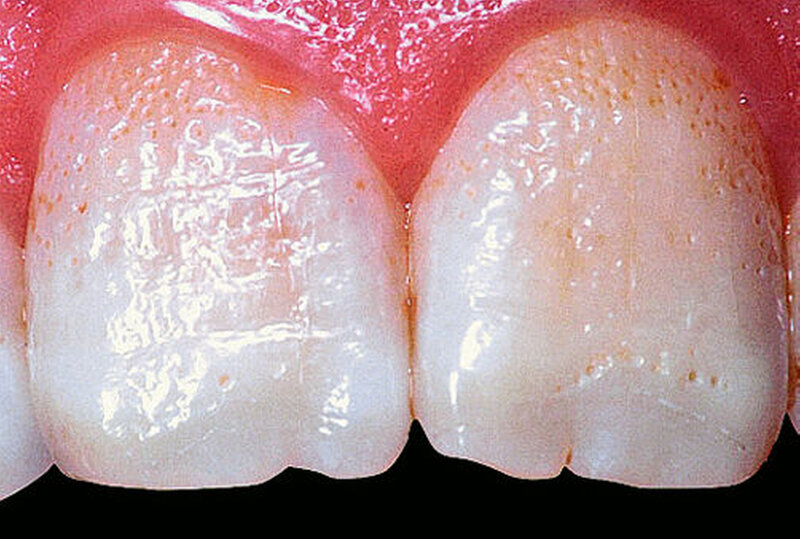

Bei dieser genetisch bedingten Schmelzdysplasie sind in der Regel alle Zähne einer oder beider Dentitionen betroffen, und es ist ein bilateralsymmetrisches Erscheinungsbild vorhanden. Die Ausprägung der Schmelzdefekte kann von Zahn zu Zahn und von Generation zu Generation variieren (Abbildungen 1a bis 1c). Die Struktur des Dentins ist nicht verändert. Die Schmelzdefekte treten als Grübchen von unterschiedlicher Größe in mehr oder weniger normal dickem Schmelz in Erscheinung (Abbildung 2a). Durch Einlagerung von Farbstoffen in diese Grübchen können die Schmelzveränderungen ästhetisch störend wirken (Abbildung 2b). Ähnliche grübchenartige Schmelzhypoplasien können bei Patienten mit Rachitis, Pseudohypoparathyroidismus oder Epidermolysis bullosa beobachtet werden. Bei der hypoplastischen Form der Amelogenesis imperfecta ist die Schmelzhärte normal, die Schmelzdicke jedoch reduziert. Der grübchenartige Typ weist als Ausnahme eine fast normale Schmelzdicke auf (Abbildungen 3 und 4).

Je nach Typ kann der Schmelz an bestimmten Zahnstellen völlig fehlen. Deshalb kann die Zahnform bereits beim Zahndurchbruch stark verändert sein.

Die Amelogenesis imperfecta kann neben der hypoplastischen Form in eine hypomaturierte Form und eine hypokalzifizierte Form eingeteilt werden. Auch Kombinationen der verschiedenen Formen der Amelogenesis imperfecta wurden beschrieben. Bei der hypomaturierten Form ist die Schmelzhärte weicher als normal, die Schmelzdicke entspricht beim Durchbruch der Zähne der Norm. Bei der hypokalzifizierten Form ist der Schmelz sehr weich und die Schmelzdicke beim Zahndurchbruch normal. Deshalb sind vor allem bei der hypomaturierten und hypokalzifizierten Form die Abrasion und Attrition stark erhöht. Bei beiden Formen ist die Zahnfarbe beim Durchbruch der Zähne opakweiß bis gelblich. Mit zunehmendem Alter werden die Zähne braun. Die Prävalenz der Amelogenesis imperfecta beträgt je nach Population und Typ zwischen 1: 700 bis 1 : 20.000.